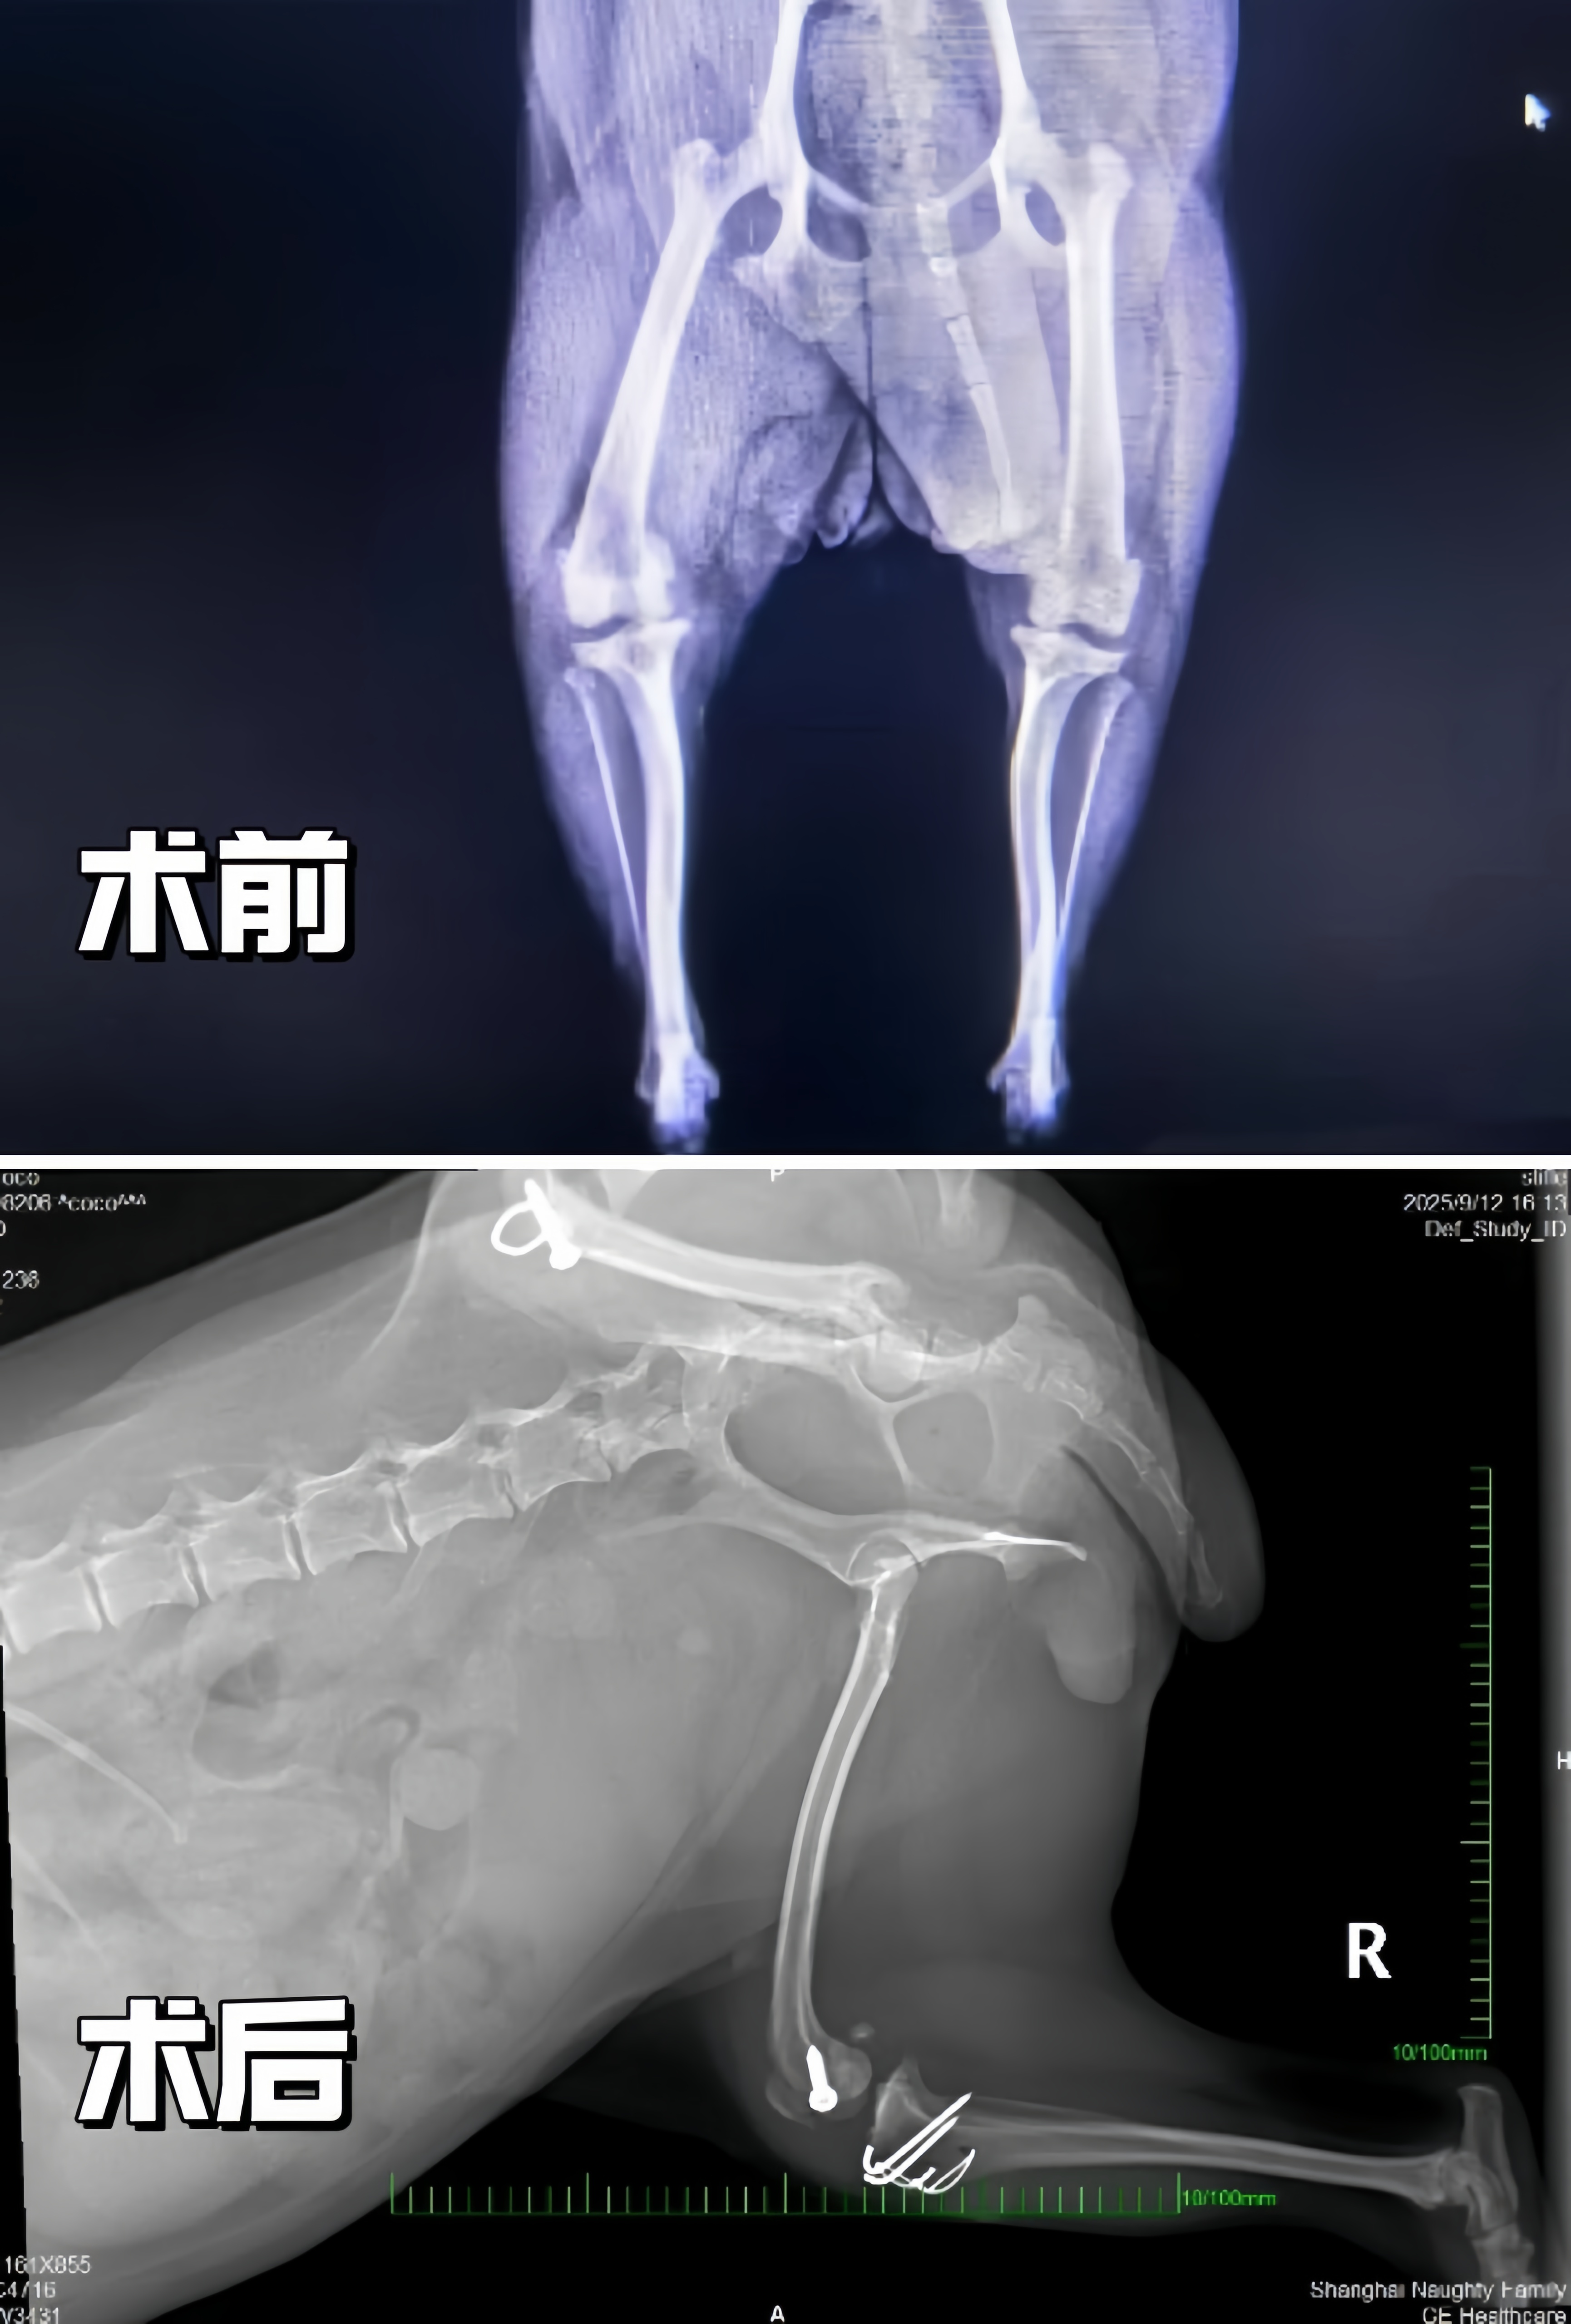

髌骨脱位是一种常见疾病,尤其在小型犬中更为多发。按严重程度分为1-4级。Coco左侧已达最严重的4级,意味着髌骨完全脱位且无法自行复位,伴随骨骼畸形和关节磨损;右侧为3级,髌骨频繁脱位但可手动复位。若不及时手术,Coco将面临关节炎加重、肌肉萎缩甚至有可能终身残疾的风险。

心脏彩超显示Coco存在粘液瘤性二尖瓣疾病(ACVIM B1期)和轻度二尖瓣反流,这一发现为手术麻醉风险评估提供了关键依据。影像学检查进一步确认了双侧髌骨脱位伴关节磨损,关节炎,左侧胫骨和股骨存在畸形。凌凤俊医生解释:“Coco的骨骼畸形是髌骨脱位反复发作的根本原因。传统手术需截骨矫正,创伤大、恢复慢。我们决定采用微创技术,以生物力学原理为核心进行髌骨复位,最大限度减少组织损伤。”

在充分的术前准备与主人信任的支持下,凌凤俊医生先后为Coco顺利完成左、右双侧髌骨修复手术。手术创口小、未进行大规模截骨,Coco术后精神状态与食欲良好,恢复平稳。为免爱犬长途奔波,主人选择留沪直至完成两次手术。目前Coco已顺利出院,步态显著改善,未出现感染及其他并发症。